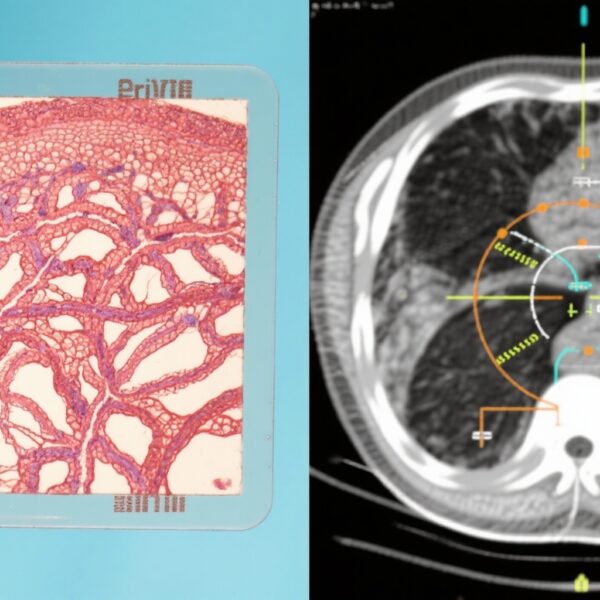

导管原位癌(DCIS)是一种非侵袭性乳腺癌,其特征是恶性细胞局限于乳管内。其自然病程具有异质性,从不太可能进展为浸润性癌症的惰性病变到复发风险高的侵袭性亚型不等。标准治疗通常包括保乳手术(广泛局部切除,WLE),通常随后进行放疗以降低复发风险。然而,常规应用放疗可能导致低风险患者的过度治疗,使他们暴露于不必要的副作用而无明显益处。

因此,个性化治疗策略对于平衡复发预防和治疗不良反应至关重要。12基因表达谱(称为DCIS评分,DS)作为一种有前景的分子工具,可用于分层DCIS风险并指导放疗决策。本研究首次前瞻性地评估了DS指导的术后放疗推荐的肿瘤学结果。